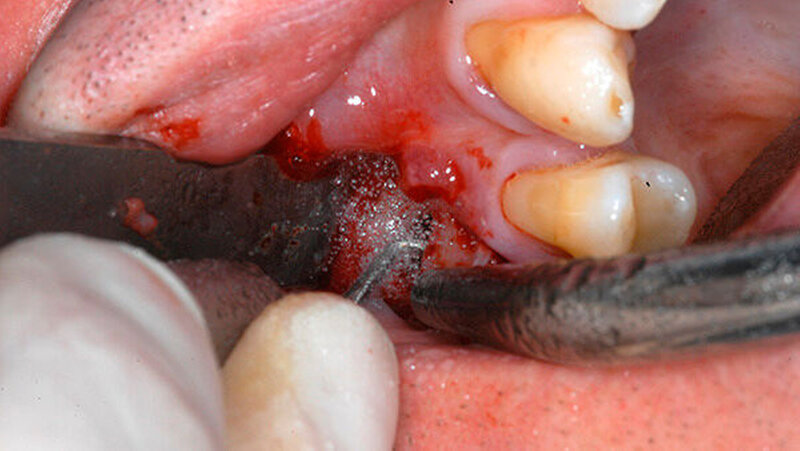

Um die mesiobukkale Wurzel freizulegen, wurde der Knochen darüber entsprechend entfernt (Abbildung 2) und eine Wurzelspitzenresektion an der mesiobukkalen Wurzel Zahn 16 durchgeführt. Das Granulationsgewebe konnte vollständig entfernt werden und wurde für eine histopathologische Untersuchung eingeschickt.

Mit einem ultraschallgetriebenen diamantierten, abgewinkelten Instrument wurden beide Wurzelkanäle der mesiobukkalen Wurzel von retrograd präpariert (Abbildung 3). Das frakturierte Instrument konnte so dargestellt (Abbildung 4) und entfernt werden.